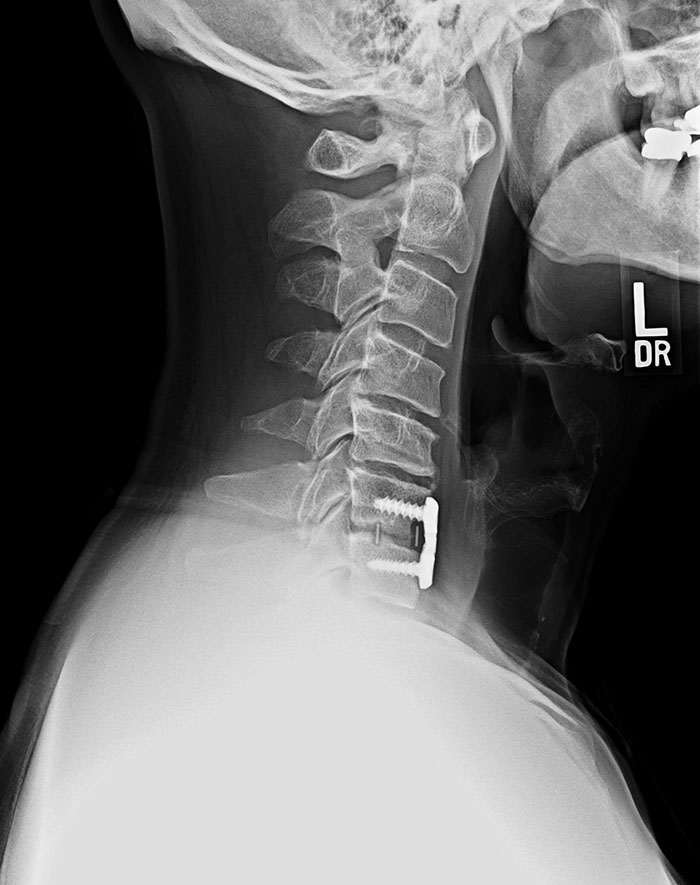

Рентген с устройством, которое фиксирует шею после перелома позвонков